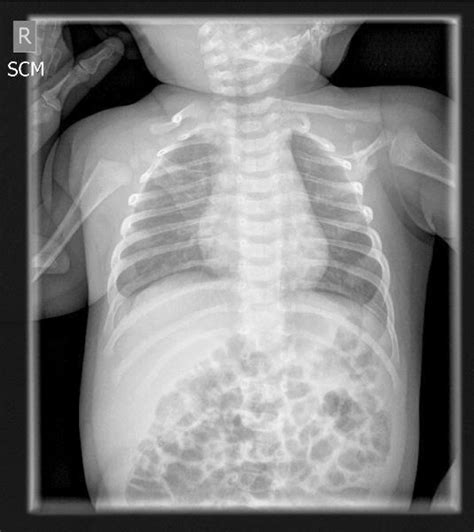

A Baby X-ray is a diagnostic imaging test that uses a small amount of radiation to create images of the bones, organs, and tissues within the body. Infants are not miniature adults; their bodies are constantly growing and changing, which is why pediatric imaging requires specialized care. Doctors typically request an X-ray for several common reasons:

- Respiratory Issues: If a baby is struggling to breathe, wheezing, or has a persistent cough, an X-ray can help identify conditions like pneumonia, bronchiolitis, or other lung infections.

- baby x ray pictures